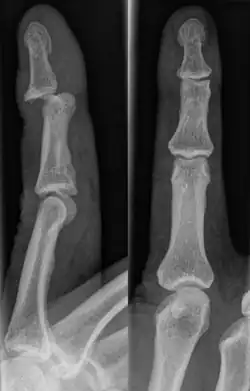

Jammed finger is a common term used to describe various types of finger joint injuries. It happens from a forceful impact originating at the tip of the finger directed towards the base. This type of directional force is called axial loading. It occurs most often when the finger is fully extended. This kind of impact can stretch or strain the ligaments in the joint beyond their normal limits. The severity of damage to the finger increases with the amount of force on the fingertip.[1] In severe cases, injury to bone may occur. When experiencing a jammed finger, the extent of injury is not always obvious and one should be evaluated by a medical professional.[2] Toes may become jammed as well, with similar results.

There are a variety of possible signs indicating a jammed finger. These depend on the severity of the injury.[3] They may include swelling, reduced joint flexibility, pain, tenderness, and joint deformity.[1] There may also be discoloration of the skin due to bruising. These symptoms usually persist for a few weeks.[3] In some cases, the damage and its effects can last for years.[4] Initial signs of a dislocation include abnormal bumps or projections at the joint. There may also be an audible popping noise when the injury occurs.[5] Fractures are indicated by abnormal protrusions along the bone,[6] where the bone itself appears split or twisted.

A jammed finger can generally be diagnosed by a physical examination. Bone or joint deformity may indicate potential dislocations or fractures.[6] The basic structure of the finger includes three bones with joints in between each.[9] The joint closest to the tip is the distal interphalangeal (DIP) joint. The next joint, moving closer to the hand, is the proximal interphalangeal (PIP) joint. The thumb differs by only having two bones and one interphalangeal joint.[10]

The injured finger may be examined to determine where the pain is worst.[3] If the finger is sprained or dislocated, pain will be worse at the joint rather than the bone.[3] Due to the risk of dislocations or fractures, X-rays should be conducted prior to testing joint stability. This allows for prior detection of a dislocation or fracture.[3] It is recommended that a variety of views (lateral, oblique, and anteroposterior) are observed.[3] In extremely painful cases, a digital nerve block may be done to better assess the finger. This is where anesthetic is injected to either side of the base of the affected finger to reduce pain.[3]

Fractures

Fractures are instances where the bone's structural integrity has been compromised.[20] If a jammed finger produces a fracture, pain will be greatest at the bone as opposed to the joint.[2] There may also be visual deformation of the bone itself.[6] As with any skeletal injury, an x-ray can be conducted to verify the presence of a fracture.[1] The distal phalanx is especially vulnerable to avulsion fractures.[1] These avulsion fractures are common following a first time dislocation of the DIP.[1]